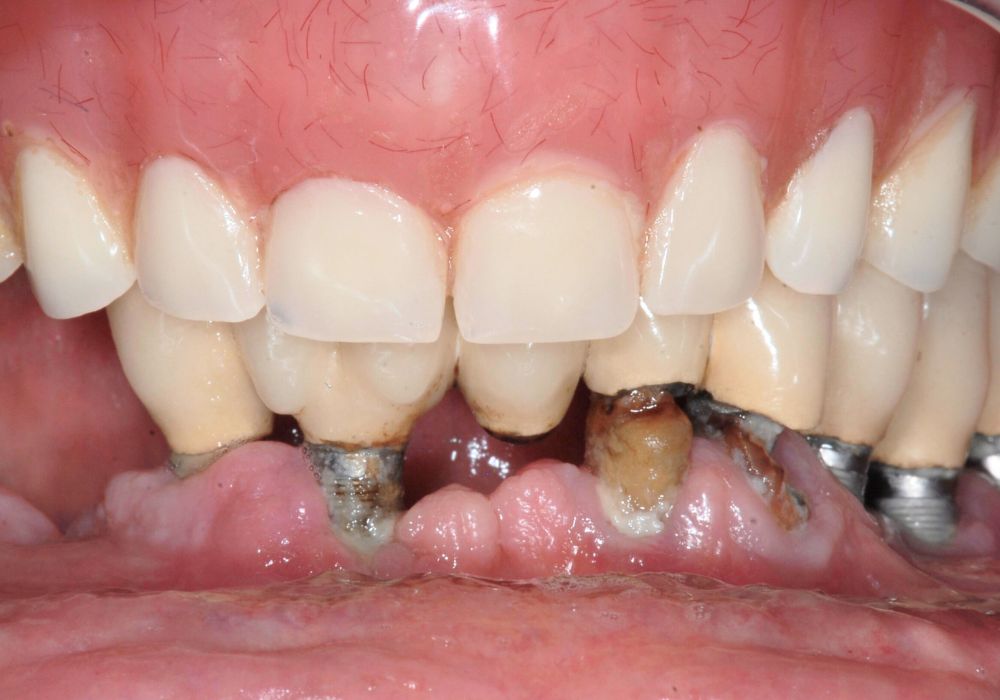

Si vous souffrez de la perte de dents et que vous cherchez une solution efficace et rapide pour retrouver un sourire esthétique, la technique All on 4 et All on 6 peut être la solution idéale pour vous. Dans cette page, nous allons vous expliquer en quoi consiste cette technique, comment elle fonctionne et si elle est la meilleure option pour vous.